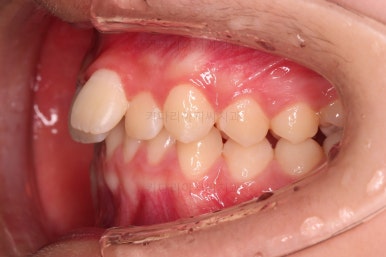

1. 초진

초진 시 입안의 모습입니다.

눈에 띄는 부분은 당연히 앞니가 삐뚤고, 앞니 하나가 앞으로 튀어나온 모습인데요.

자세히 관찰해 보면 다른 문제점들이 보입니다.

우선 위아래 앞니가 깊숙히 맞물려 있는 과개교합 양상인데요.

✅ 앵글씨 2급 부정교합

이번 환자분은 앵글씨 2급 부정교합이었는데요.

정상교합에 비해서 윗니가 상대적으로 앞에 아랫니가 상대적으로 뒤에 위치한 부정교합이 앵글씨 2급 부정교합입니다.

이번 환자분은 어금니가 위아래가 지그재그 서로 엇갈려 꽉 끼이는 교합이 아니라 1대1로 치아가 부딪혀 있는 상태였습니다.